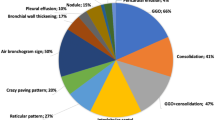

GGO was the most represented characteristic in suspected CT by COVID-19 (Table 2), it was present in 102/109 (93.6%) patients. GGO percentage volume was 19.50% with a median value of 0.64 L, statistically superior (p value < < 0.01 at Mann–Whitney test) with respect to the other volumes (emphysema volume (0.01 L) and consolidation volume (0.03 L)).

GGOs were predominantly bilateral in 89/102 (87.3%) patients with involvement in multiple lobes in 77/102 (75.5%) patients, distribution peripheral in 82/102 (80.4%) patients and multifocal/patching in 69/102 (67.7%) patients. Consolidations were found in 78/109 (71.6%) patients, predominantly bilateral in 68/78 (87.2%) patients, with involvement in multiple lobes in 53/78 (67.9%) patients, distribution peripheral in 67/78 (85.9%) patients and segmental in 33/78 (42.3%) patients.

Among quantified volumes, only GGO had a difference statistically significant between patients with suspected CT and non-suspected CT for COVID-19 (p value < < 0.01 at Mann–Whitney test, Table 2).

In Table 3, the percentage values of volumes of healthy residual lung parenchyma, emphysema, GGO and consolidations are reported considering the patients grouped for pneumonia radiological severity score.

Volume median values of healthy residual lung parenchyma were, respectively, of 93.8%, 91.1%, 77.8%, 66.0% and 60.0% for none, mild, moderate, severe and critical radiological score.

Volume median values of GGO were, respectively, of 4.1%, 6.6%, 16.0%, 26.8% and 31.2% for none, mild, moderate, severe and critical radiological score.

Volume median values of consolidations were, respectively, of 0.6%, 0.7%, 0.9%, 1.3% and 1.60% for none, mild, moderate, severe and critical radiological score.

There were differences statistically significant among the groups based on radiological severity score in terms of healthy residual parenchyma volume, of GGO volume and of consolidations volume with a p value < < 0.001 at Kruskal–Wallis test (Fig. 2).